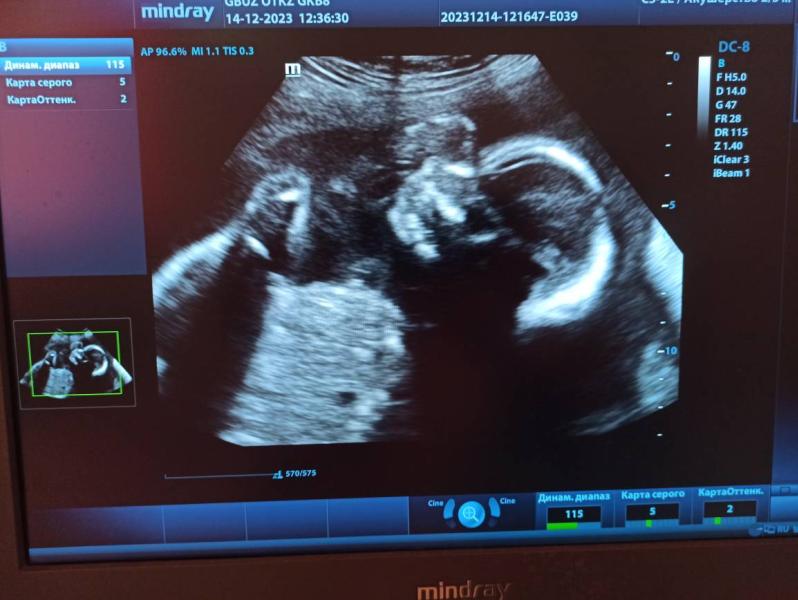

Пдр на 24 марта, надеюсь может чуть раньше🤞🏻